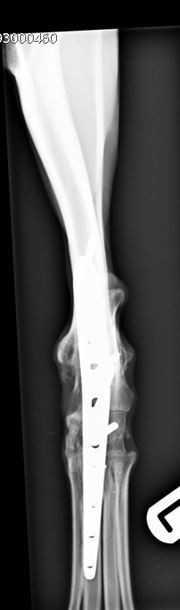

Six-weeks following surgery radiographs revealed excellent progression of arthrodesis and no evidence of implant associated problems. Normal exercise was gradually re-introduced at this point. Pantarsal arthrodesis was successful for salvaging a pain-free hindlimb after a potentially catastrophic fracture of the articular surface of the talus of a greyhound.

Figure 4. Six-week post-operative craniocaudal view